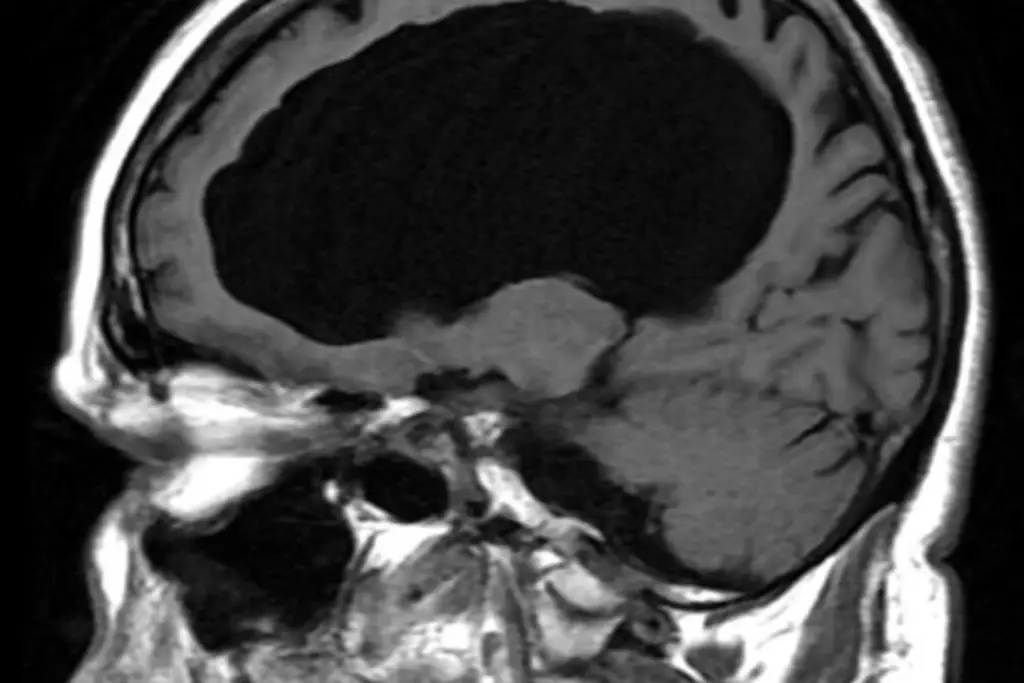

Explicó que en México, tan solo en 2024, se registraron 18.019 decesos por enfermedades cerebrovasculares, lo que posicionó a estas condiciones como la séptima causa de muerte a nivel nacional.

Además, de acuerdo con la Secretaría de Salud, cada año se registran 170.000 casos de infarto cerebrovascular y aunque el mayor número de fallecimientos se han registrado en personas mayores de 65 años, ahora los casos se presentan a edades menores.